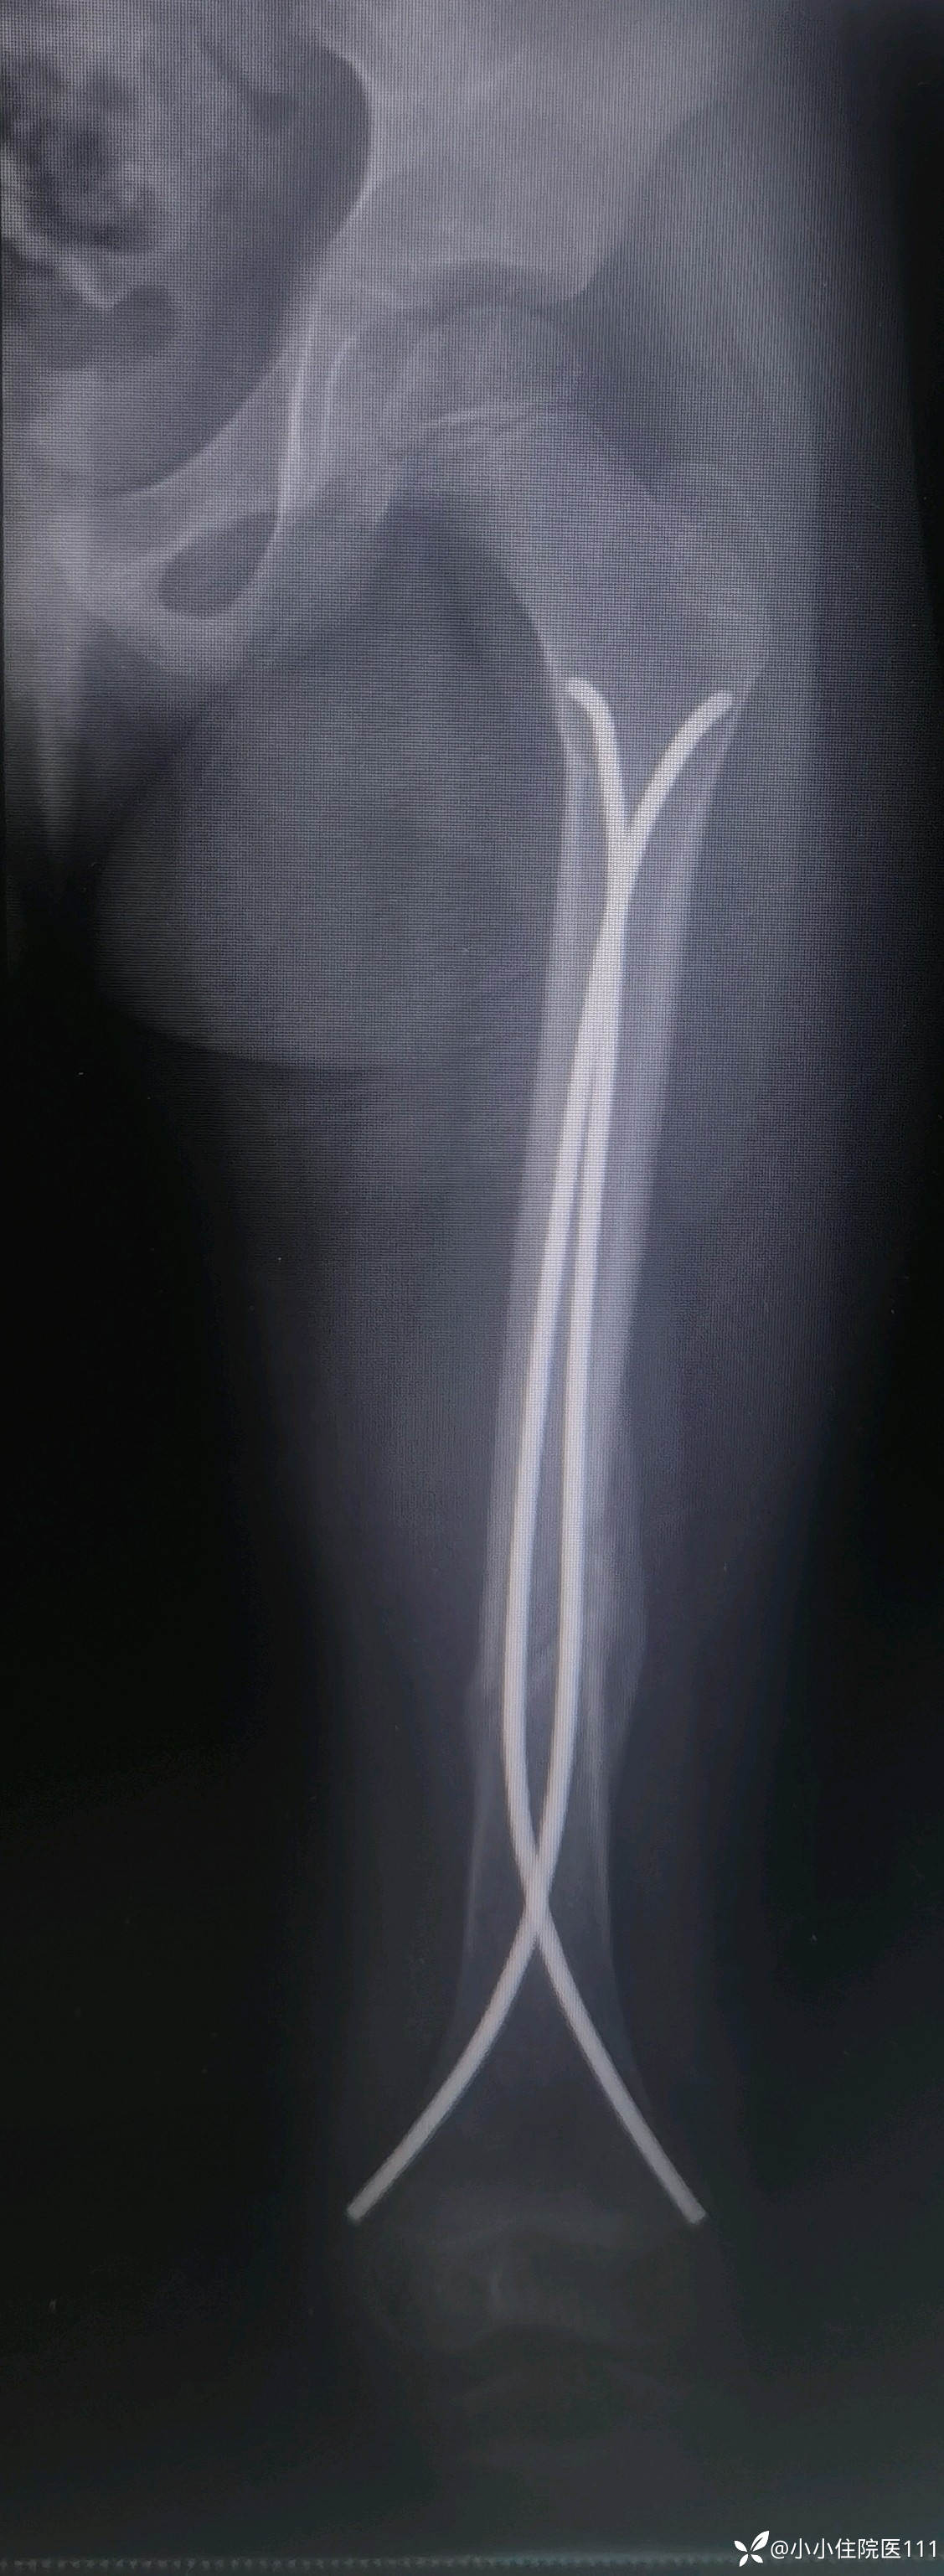

(2023-06-09)复查左股骨正侧位片

(2023-07-09)复查左股骨正侧位片

(2023-08-28)复查左股骨正侧位片